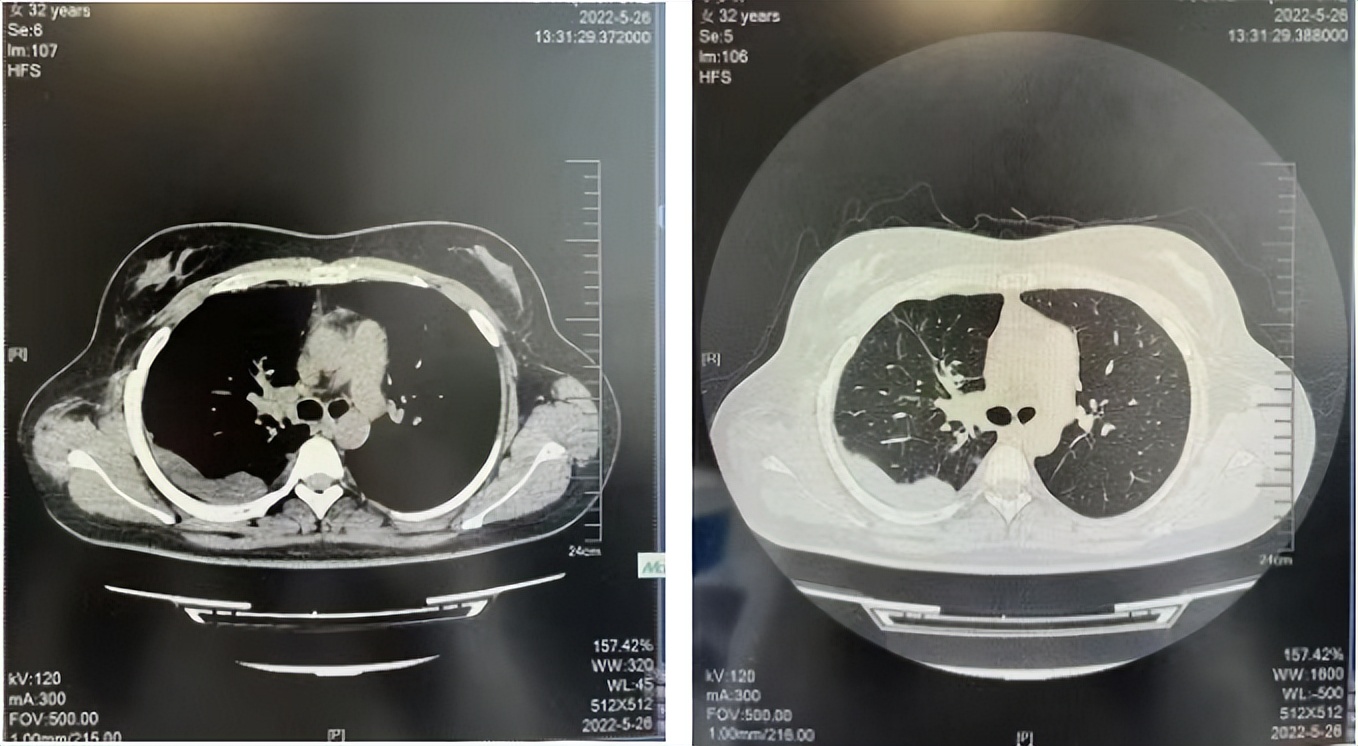

临床诊断:右肺上叶恶性肿瘤rT0N0M1a IVA期(第9版分期);恶性胸腔积液。

诊疗经过:2022年5月始口服克唑替尼3个月,出现肝功能异常(DILI 2级伴临床症状),改用恩沙替尼靶向治疗至今,目前评效为维持PR。恩沙替尼应用期间出现轻度肝功能异常(DILI 1级),对症处理后好转。截止目前PFS 33个月。

2022.08

2023.05

2024.12